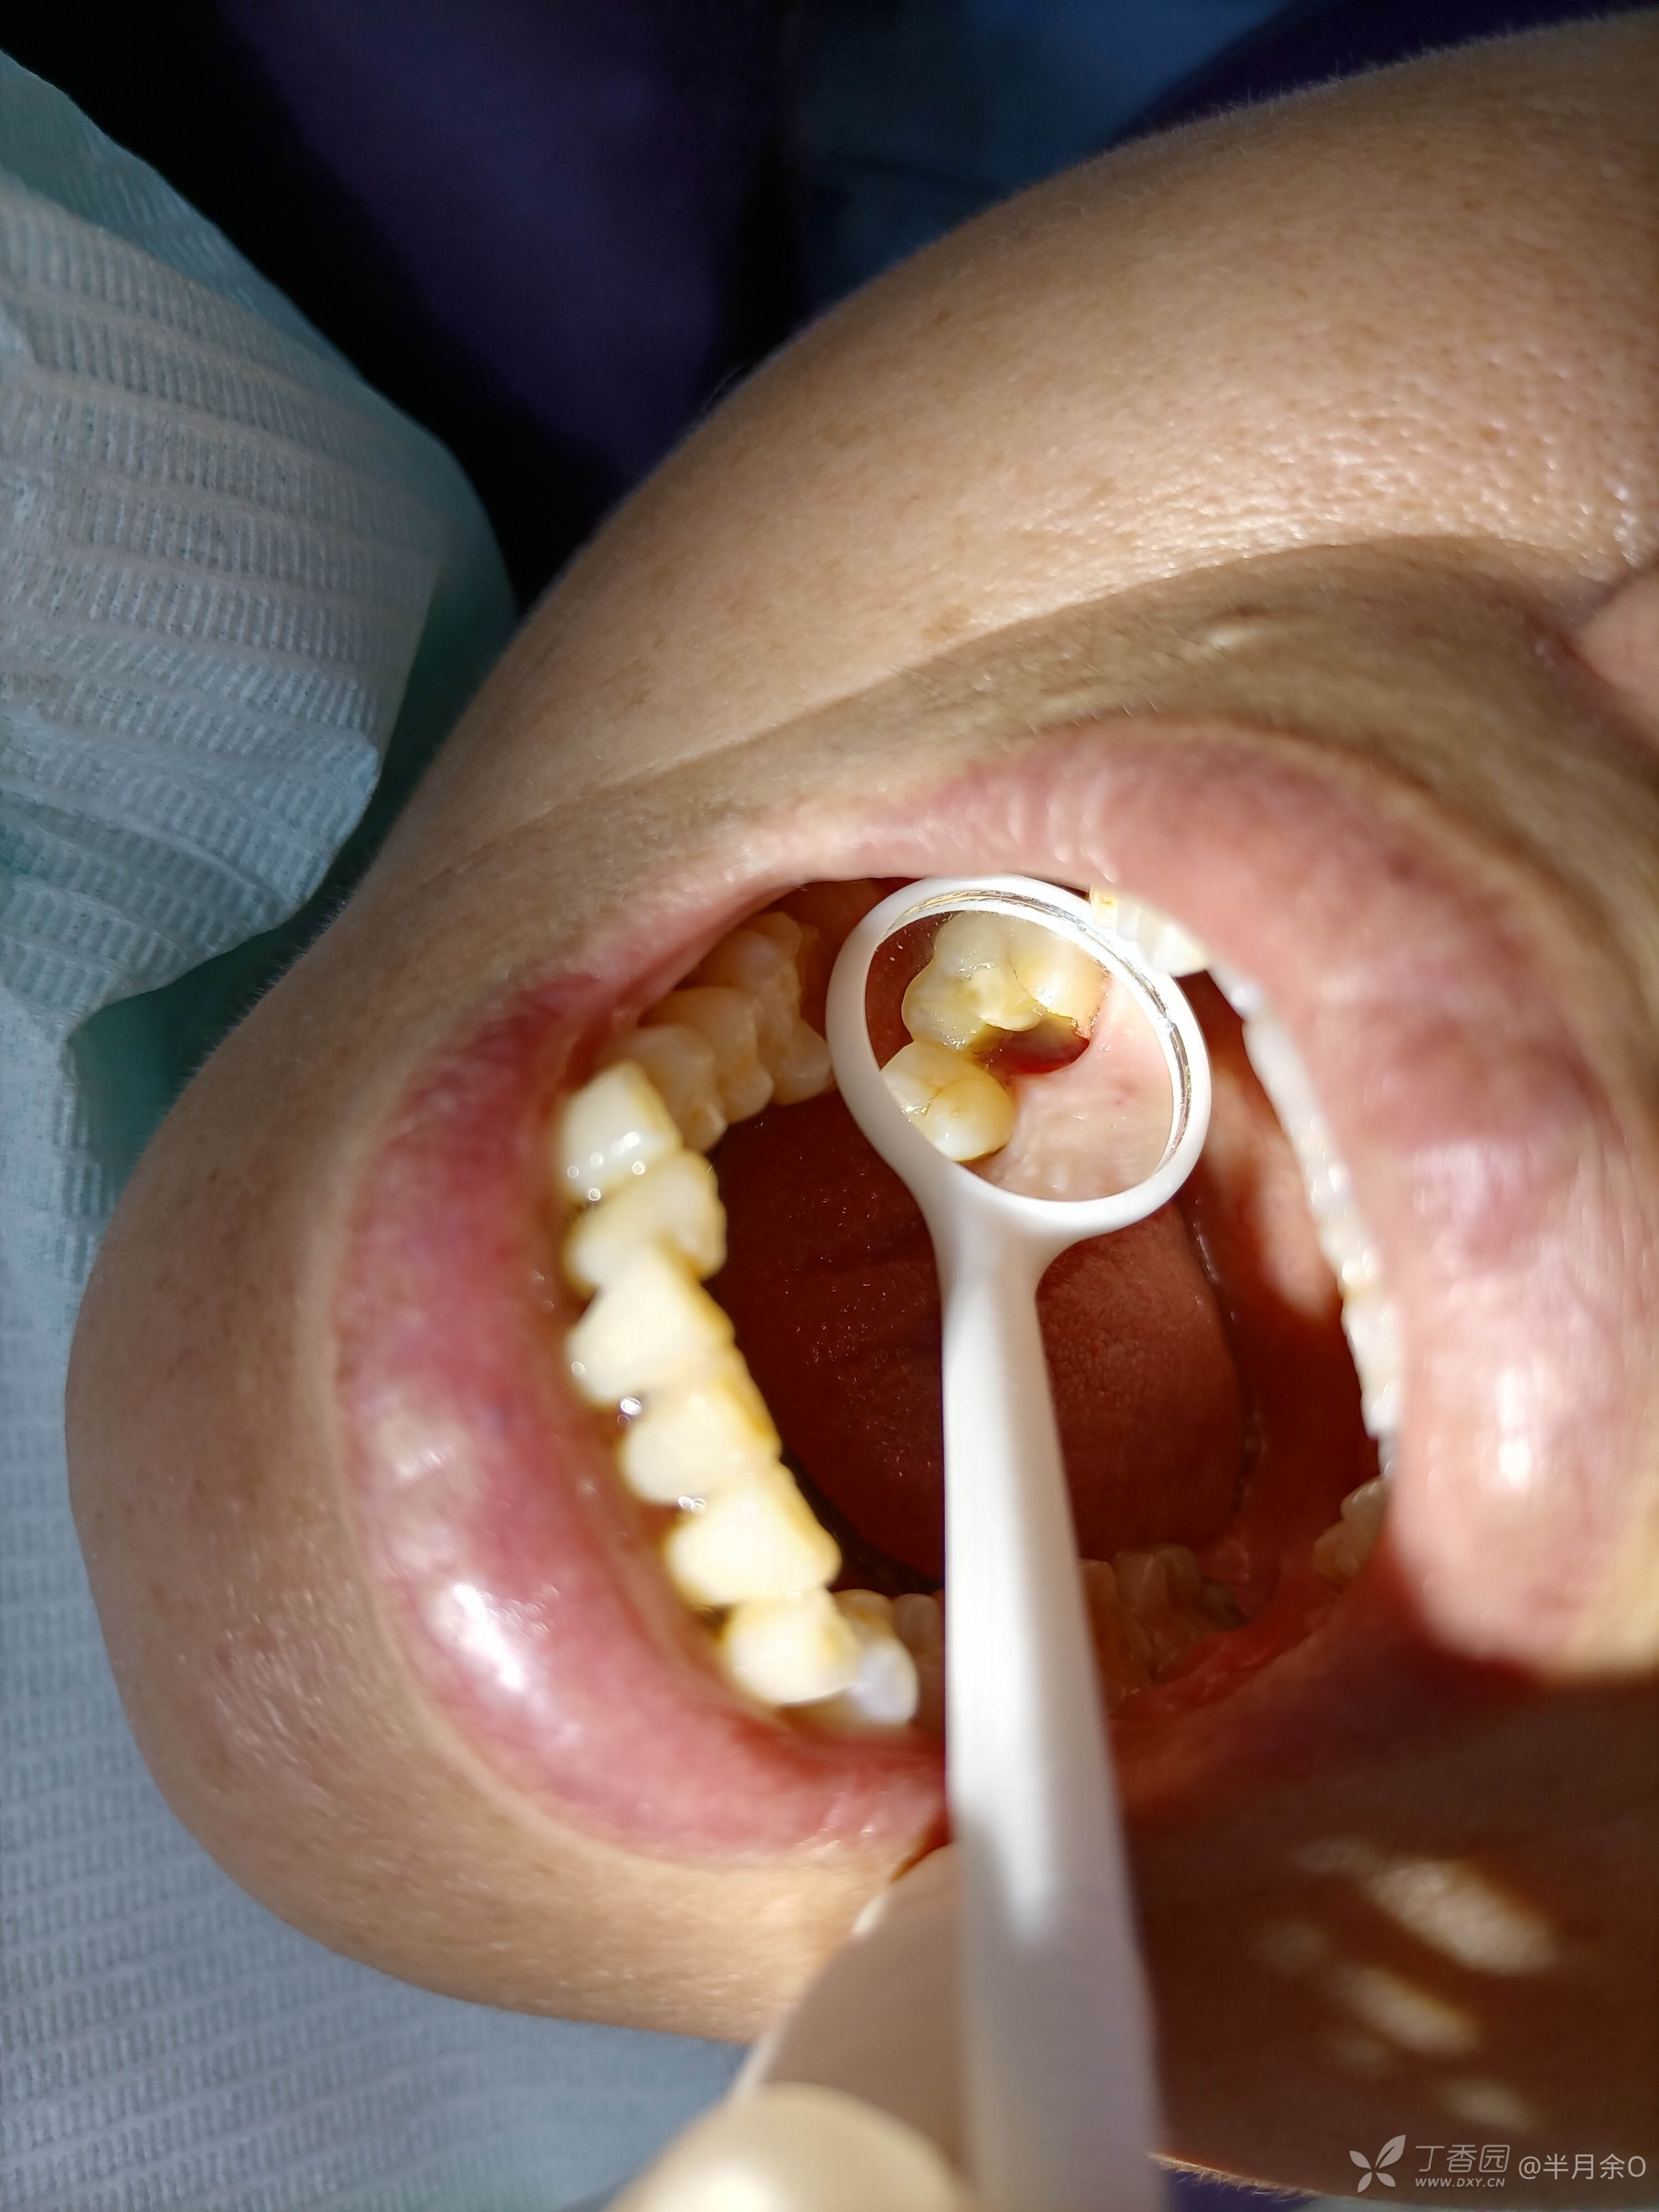

患者年龄60,2021.5.29因牙痛,夜间痛就诊,右上6检查隐裂,建议根管治疗后冠修复,患者要求拔除,考虑后下午来治疗6.6根备,6.17根充,患者拒绝冠修复,7.13腭尖折断至龈下约2mm,拔除腭尖,分享。